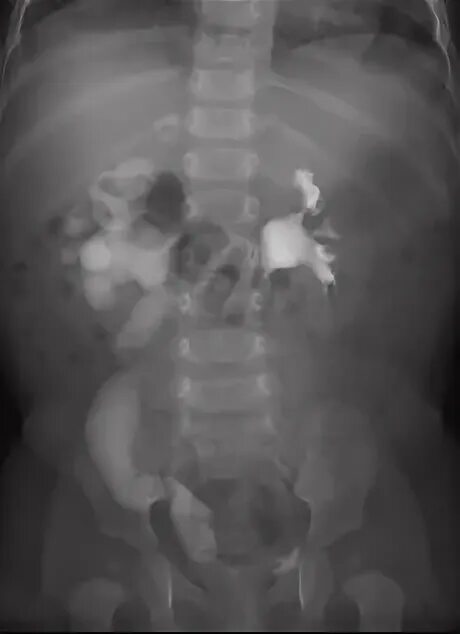

Мегауретер у детей что это